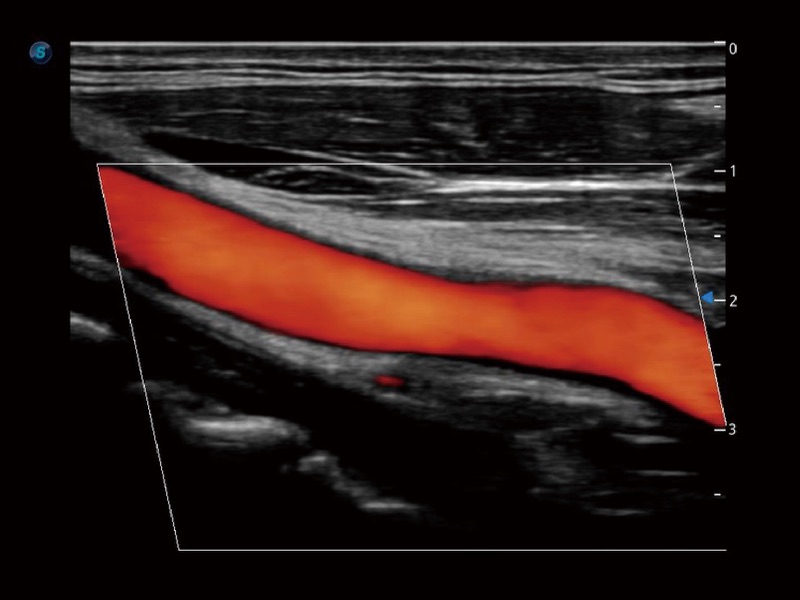

高分辨率血流成像技术提高了对低速血流信号的检测能力。在提高空间分辨率的同时,也克服了血流外溢现象,为用户提供更加真实的血流动力学信息。